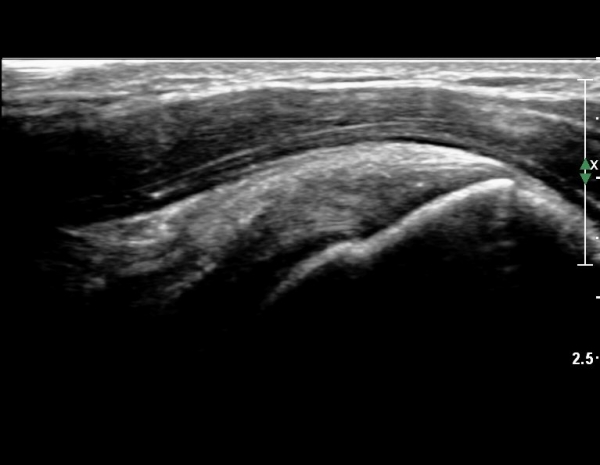

°ß°©ÇÏ±Ù°Ç ÇϺο¡¼­´Â ÀÌ»ó ¼Ò°ßÀÌ °üÂûµÇÁö ¾Ê´Â´Ù(»çÁø 4).